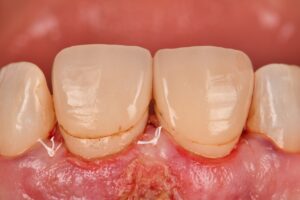

A youthful width:height ratio for central incisors ranges from 75:100 to 80:100.

We were successful in modifying both gingival and osseous parameters based on a DSD-based protocol.